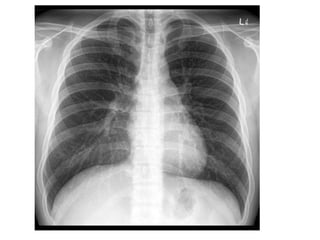

X-RAYS

• Normal chest xray